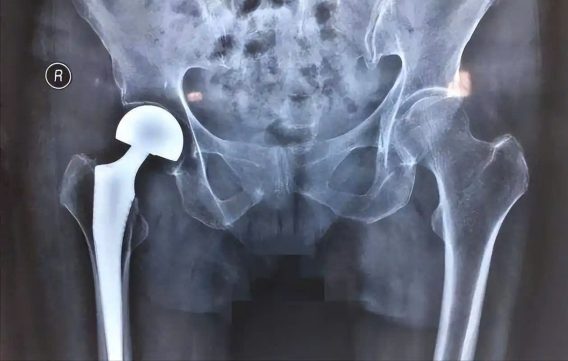

Hợp kim titan thể hiện phản ứng đào thải tối thiểu khi tiếp xúc với mô người và thường được sử dụng trong cấy ghép chỉnh hình và phục hình răng, lớp màng oxit bề mặt của chúng giúp cách ly chúng khỏi các chất lỏng ăn mòn và giảm viêm, do đó phù hợp cho việc cấy ghép lâu dài.

Hợp kim titan có độ bền cơ học tương tự như xương tự nhiên và mô đun đàn hồi thấp, giúp giảm tác động che chắn ứng suất lên mô xương xung quanh sau khi cấy ghép và thúc đẩy quá trình lành xương, khả năng chống mỏi của chúng cũng kéo dài tuổi thọ của khớp giả.

Hình ảnh hạn chế: Hợp kim titan có thể tạo ra các hiện vật kim loại trong quá trình chụp CT hoặc MRI, làm ảnh hưởng đến độ rõ nét của hình ảnh ở các vùng như khớp háng và cột sống, trước khi chụp CT tăng cường, hãy thông báo cho bác sĩ về bất kỳ implant nào bạn đang có.

Nguy cơ phẫu thuật thứ phát: Có thể cần phải phẫu thuật chỉnh sửa ở thanh thiếu niên do xương phát triển hoặc implant bị lỏng lẻo, có khả năng gây ra chấn thương mới, bệnh nhân cao tuổi hoặc những người bị loãng xương có nguy cơ gặp các biến chứng như gãy xương quanh chân giả.